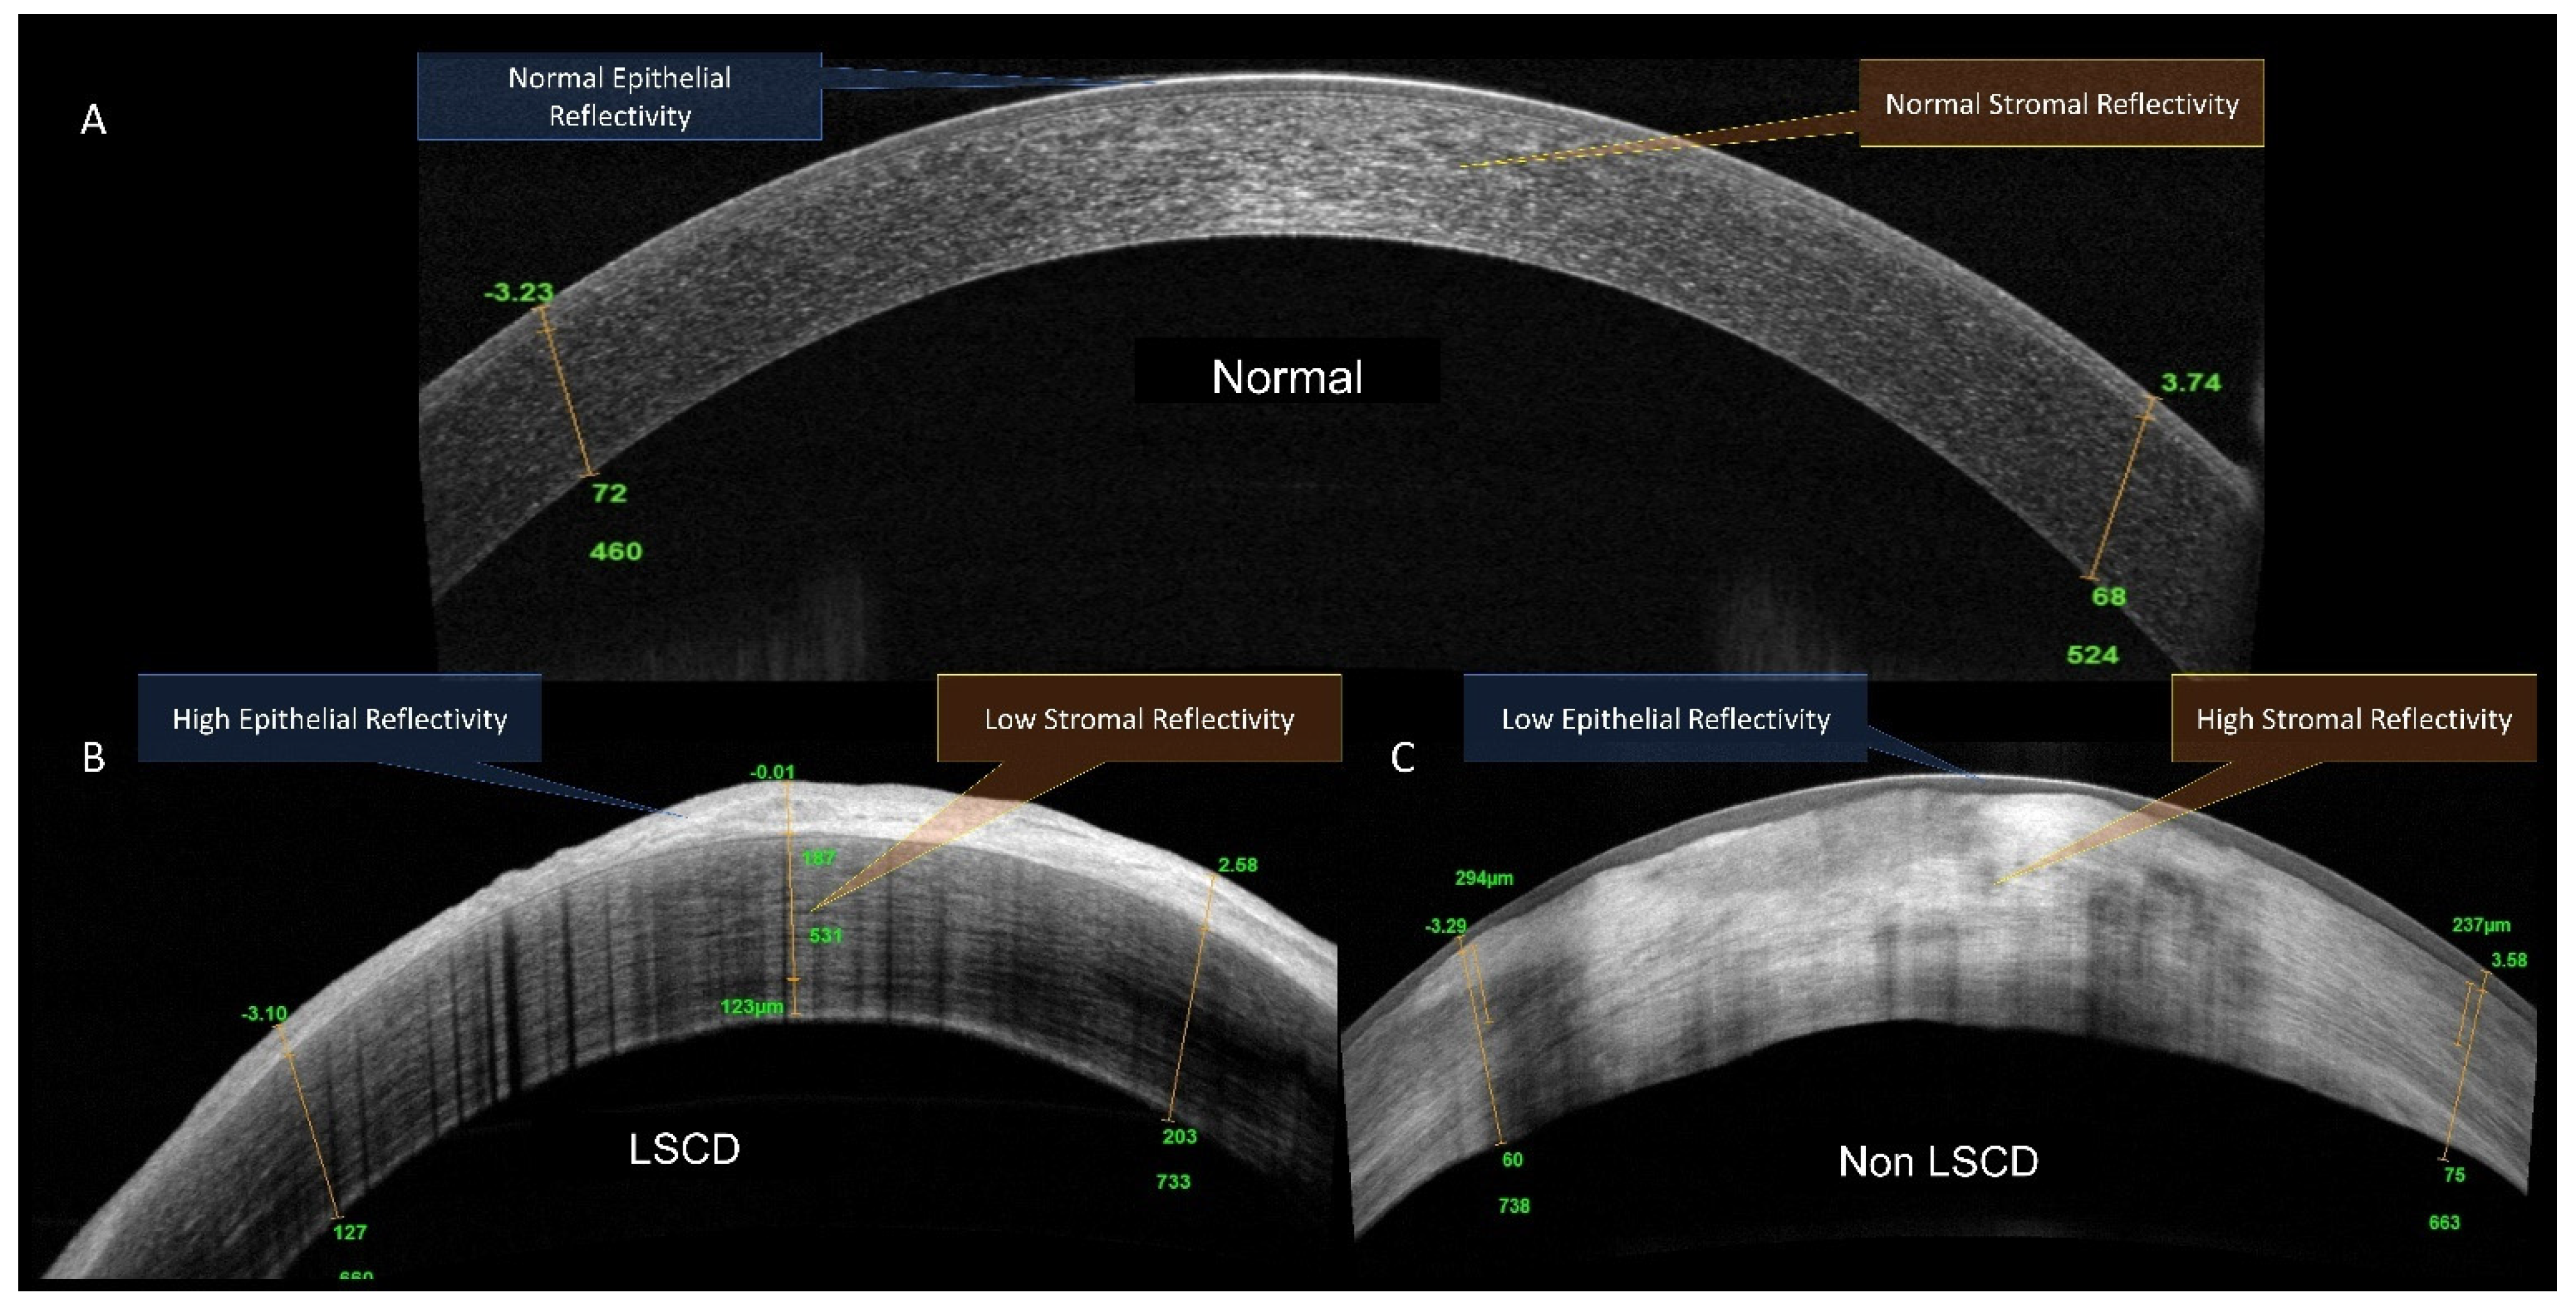

3.2. HR-OCT Imaging Parameters Diagnostic of LSCD